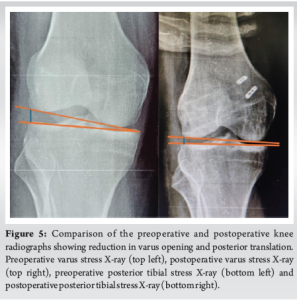

Both limbs were secured in the respective tunnels with the help of an adjustable-loop cortical suspensory fixation implant. Final tensioning was done in a limb position of 30° flexion, slight valgus, and neutral rotation. Final intraoperative stability testing showed reduced lateral opening with varus stress, and the posterior drawer was reduced to Grade 1. Postoperative radiographs showed a reduction in posterior translation and varus opening (Fig. 5). Postoperative rehabilitation involved 6 weeks of non-weight bearing, with range of motion limited to 90° for the first 2 weeks, followed by range of motion as tolerated. The patient began weight-bearing at 6 weeks along with gait training and proprioception exercises. On clinical examination at the 3-month follow-up, external rotation asymmetry was restored to normal, the varus stress test was negative and complete knee range of motion was achieved (Fig. 6). The Posterior drawer test continued to show a Grade 1 laxity, but the patient did not have any instability or symptoms of PCL deficiency. At the 6-month follow-up, the patient was walking pain-free without any limp, had near-normal squatting, and was able to carry out all activities of daily life. At the 1-year follow-up, the Lysholm score was 90/100, the International Knee Documentation Committee (IKDC) score was rank B (near normal), and the patient could comfortably engage in low-to-moderate demand sports [12,13].